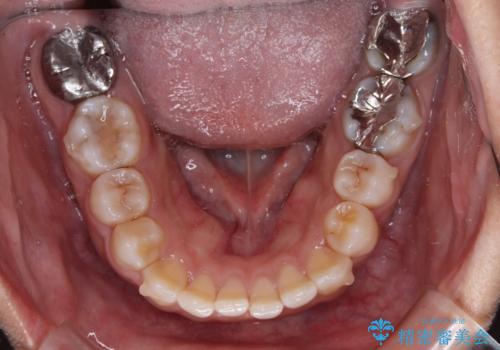

- 上下前歯の叢生を気にして来院された患者様です。

軽度な叢生であり、安価で短期間の治療を規模されていたため、インビザライン・モデレートを用いて矯正治療を行うこととしました。

インビザライン・モデレートは、製作できるアライナーの枚数に制限があるため、移動可能な量に限りがあるものの、インビザライン・ライトよりも枚数が多いため、幅広い症例に対応可能です。